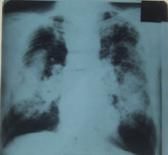

Radiografía PA de Tórax: Técnica 2,

opacidad de ápice izquierdo tipo C de la Clasificación

Internacional de radiografías de Neumoconiosis de la

OIT de 1980, y opacidades micronodulares redondeadas diseminadas

clasificación 2/3 r/r. Electrocardiograma: normal.